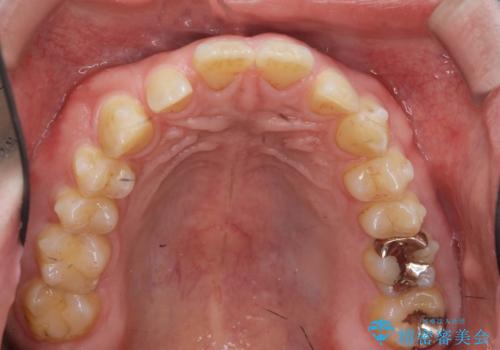

ディープバイトのマウスピース矯正

- 飛び出してしまい、隙間のある前歯をきれいに並べたい、と矯正治療を希望され来院されました。

上顎前歯を後方に引き、隙間を閉じるためには下顎前歯の絶対的な圧下を行い、深い噛み合わせを改善することが必要です。

前歯でチューイーをしっかり噛み、咬合圧を伝えたことで下顎前歯が圧下し、上顎前歯の隙間を閉じることができました。